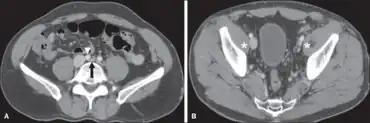

May–Thurner syndrome in the broader disease profile known as nonthrombotic iliac vein lesions (NIVLs) exists in the symptomatic ambulatory patient and these lesions are usually not seen by venography. Morphologically, intravascular ultrasound (IVUS) has emerged as the best current tool in the broader sense.[9] Functional testing such as duplex ultrasound, venous and interstitial pressure measurement and plethysmography may sometimes be beneficial. Compression of the left common iliac vein may be seen on pelvic CT.